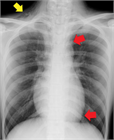

1. 若年でやせ型の男性の胸痛では、特発性縦隔気腫を鑑別診断に挙げることを勧める(推奨度2)

1. 縦隔気腫の誘因となるようなエピソードの後や原因となるような疾患を持つ症例で、胸痛や息切れ・呼吸困難などの症状がみられた場合には、縦隔気腫を鑑別に挙げることを勧める(推奨度2)

1. 胸部X線写真(CXR)で検出しきれない特発性縦隔気腫が少なからずあるため、CXRが正常範囲と判断されても、特発性縦隔気腫が疑われる場合は、積極的に胸部CTを撮影することを勧める(推奨度2)